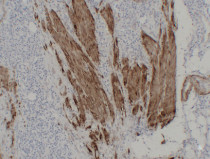

ARG66482 anti-Calponin 1 antibody IHC-P image

Immunohistochemistry: Paraffin-embedded Human fibroid stained with ARG66482 anti-Calponin 1 antibody at 1:200 (4°C, overnight). Antigen Retrieval: Citric acid buffer (pH 6.0) was used.